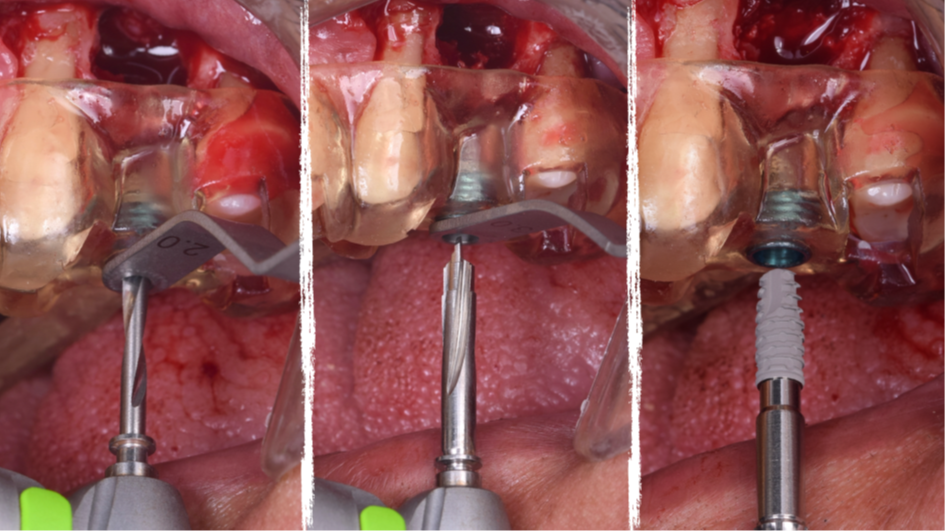

O presente trabalho tem como objetivo fazer um relato de caso clínico de reintervenção em enxerto ósseo para levantamento de seio maxilar pela técnica da janela lateral com instalação simultânea de implante Maestro Superiore.